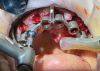

(20.) Full-arch treatment using a stackable surgical guide that employs components that attach to a foundation base, including views with the pin guide attached to the foundation base inserted over the existing dentition, the osteotomy guide attached and osteotomy being performed, the implants placed and the multi-unit abutments attached, and a prefabricated temporary prosthesis attached to the foundation base, ready to be luted to temporary cylinders for intraoral pickup, respectively.

Figure 20

(21.) Full-arch treatment using a stackable surgical guide that employs components that attach to a foundation base, including views with the pin guide attached to the foundation base inserted over the existing dentition, the osteotomy guide attached and osteotomy being performed, the implants placed and the multi-unit abutments attached, and a prefabricated temporary prosthesis attached to the foundation base, ready to be luted to temporary cylinders for intraoral pickup, respectively.

Figure 21

(22.) Full-arch treatment using a stackable surgical guide that employs components that attach to a foundation base, including views with the pin guide attached to the foundation base inserted over the existing dentition, the osteotomy guide attached and osteotomy being performed, the implants placed and the multi-unit abutments attached, and a prefabricated temporary prosthesis attached to the foundation base, ready to be luted to temporary cylinders for intraoral pickup, respectively.

Figure 22

(23.) Full-arch treatment using a stackable surgical guide that employs components that attach to a foundation base, including views with the pin guide attached to the foundation base inserted over the existing dentition, the osteotomy guide attached and osteotomy being performed, the implants placed and the multi-unit abutments attached, and a prefabricated temporary prosthesis attached to the foundation base, ready to be luted to temporary cylinders for intraoral pickup, respectively.

Figure 23